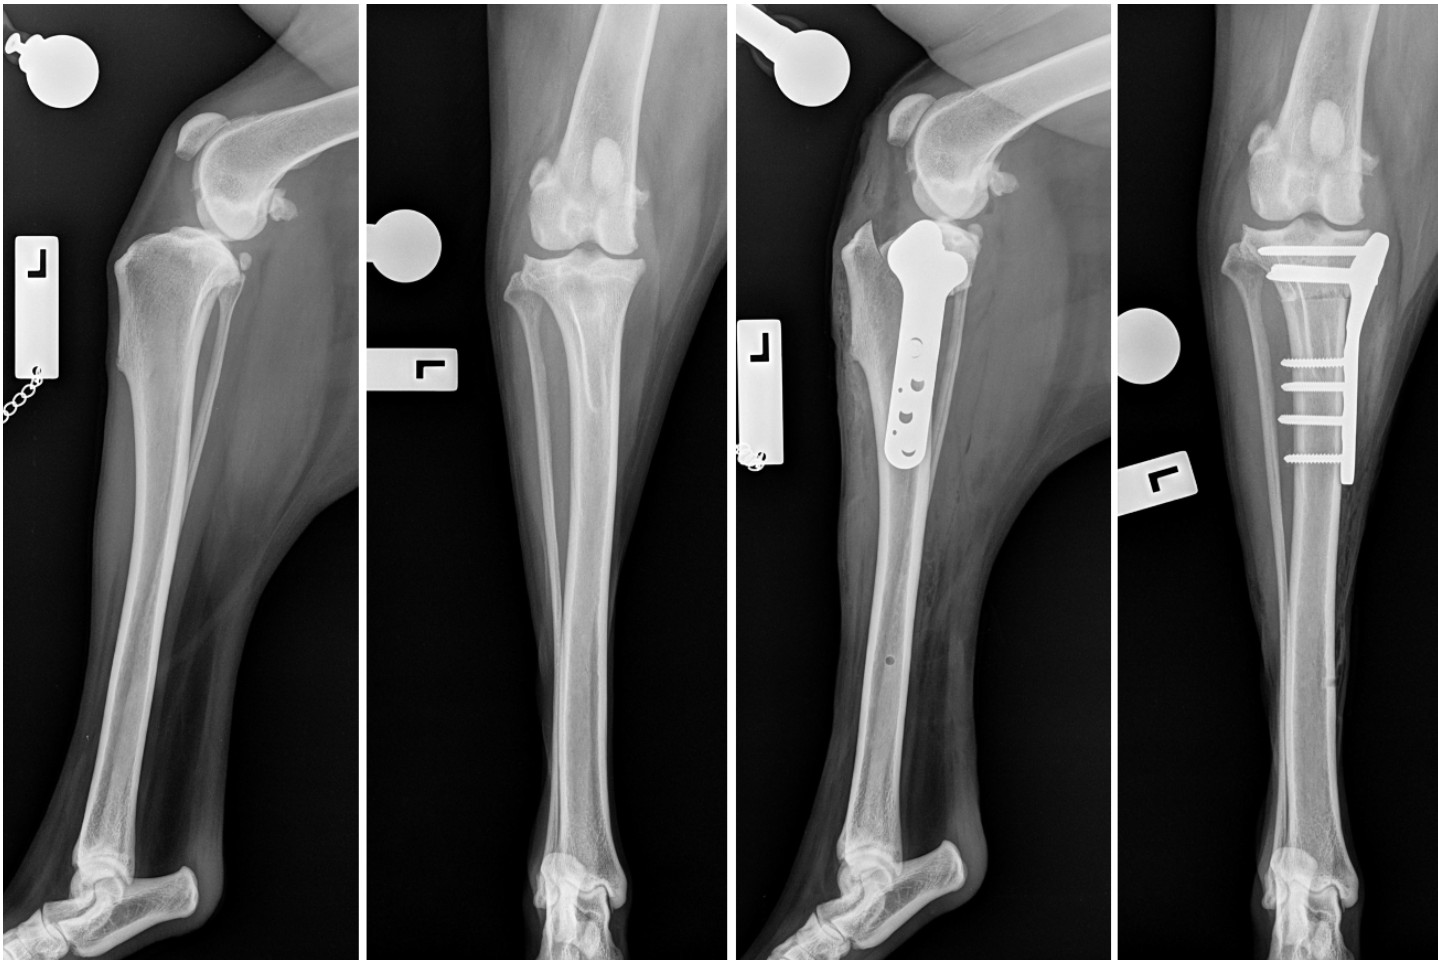

We perform the TPLO procedure for the management of cranial cruciate ligament disease. Preoperative radiographs are performed for surgical planning purposes so that we can select the appropriately sized instruments and implants. During surgery the joint is inspected, and the status of the cruciate ligament and medial meniscus are assessed. If the meniscus is torn, then removal of the torn part of the meniscus is performed to reduce pain.

Following joint inspection, a radial (circular-shaped) osteotomy is performed in the tibia and the bone fragment is rotated to flatten the slope of the tibia to ~5°. This eliminates the sliding movement between the tibia and femur and effectively stabilises the joint. Finally, a bone plate is applied to secure the bone fragments to allow bone healing.

TPLO procedure: pre- (left) and postoperative radiographs (right)